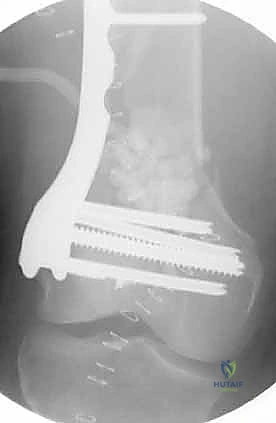

المرحلة الرابعة: التثبيت النهائي بالشرائح والمسامير (Fixation)

يتم استخدام "شرائح الإغلاق التشريحية" (Anatomical Locking Plates) المصنوعة من التيتانيوم عالي الجودة. هذه الشرائح مصممة خصيصاً لتأخذ شكل الجزء السفلي من عظم الفخذ. يتم تمرير الشريحة أسفل العضلات وتثبيتها بمسامير تغلق داخل الشريحة نفسها (Locking Screws)، مما يوفر ثباتاً ميكانيكياً هائلاً، حتى في حالات العظام الهشة.

في بعض الحالات المعقدة جداً، قد يتطلب الأمر استخدام شريحتين (Dual Plating) لضمان عدم تحرك الكسر أثناء فترة التعافي.